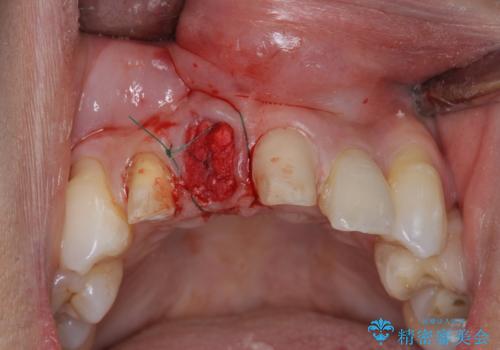

上顎4前歯は、根管治療の既往があり、虫歯も見られたことからブリッジによる治療で審美性の回復を行うとともに臨在歯の虫歯もセラミック治療を行っていきます。

欠損部の歯ぐきの量が足りない場合は、移植を行い歯肉を増大させることもありますが、今回は仮歯で様子を見た結清掃性・審美性に問題が出なかったので行いませんでした。